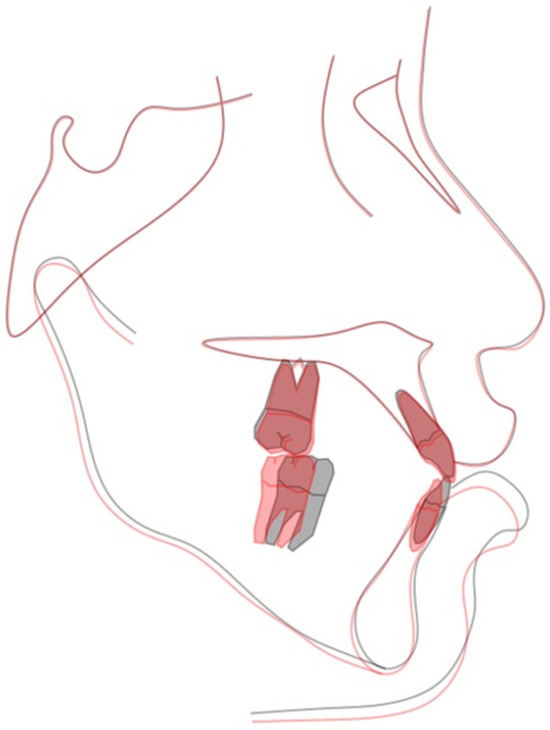

2.4. Treatment Progress